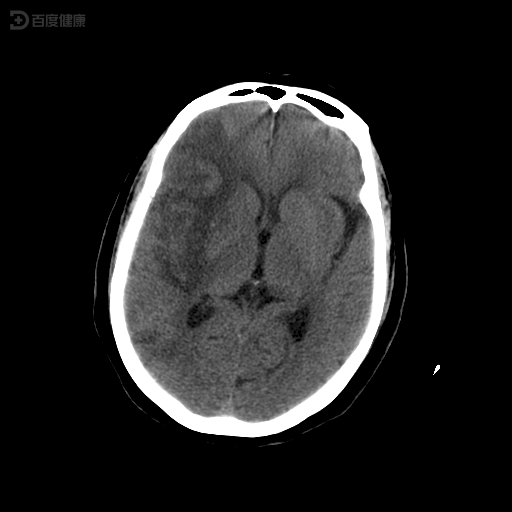

手术前后对比图如下:患者近10天内发作脑梗死2次,虽均为小梗塞,但ct

图片尺寸750x772